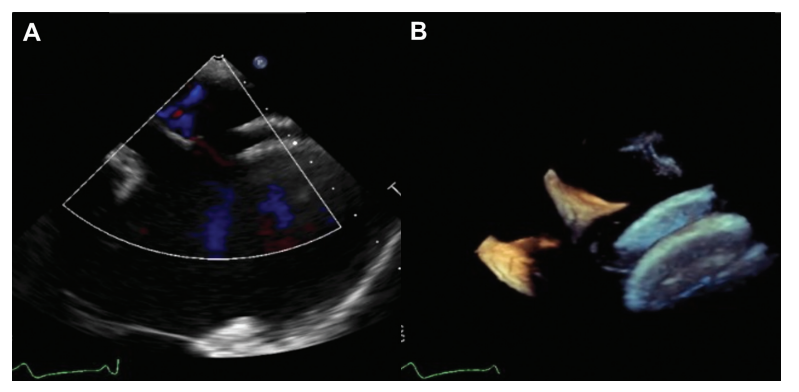

然而,三年后,她因劳累时心悸和呼吸困难入院,符合纽约心脏协会Ⅲ级标准。心电图显示持续性心房颤动。经食管超声心动图显示左向右残余分流,分流分数为43%,右心房增大,中度至重度三尖瓣反流,左心室射血分数为52%。令人惊讶的是,只有一个房间隔封堵器可见(►图1)。

图1. 术前超声心动图显示明显的心房分流(A)和单个封堵器的存在(B)。